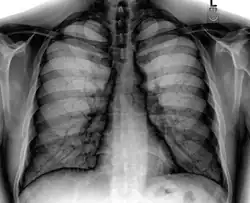

Different views (also known as projections) of the chest can be obtained by changing the relative orientation of the body and the direction of the x-ray beam. The most common views are posteroanterior, anteroposterior, and lateral. In a posteroanterior (PA) view, the x-ray source is positioned so that the x-ray beam enters through the posterior (back) aspect of the chest and exits out of the anterior (front) aspect, where the beam is detected. To obtain this view, the patient stands facing a flat surface behind which is an x-ray detector. A radiation source is positioned behind the patient at a standard distance (most often 6 feet, 1,8m), and the x-ray beam is fired toward the patient.

In anteroposterior (AP) views, the positions of the x-ray source and detector are reversed: the x-ray beam enters through the anterior aspect and exits through the posterior aspect of the chest. AP chest x-rays are harder to read than PA x-rays and are therefore generally reserved for situations where it is difficult for the patient to get an ordinary chest x-ray, such as when the patient is bedridden. In this situation, mobile X-ray equipment is used to obtain a lying down chest x-ray (known as a "supine film"). As a result, most supine films are also AP.

Lateral views of the chest are obtained in a similar fashion as the posteroanterior views, except in the lateral view, the patient stands with both arms raised and the left side of the chest pressed against a flat surface.